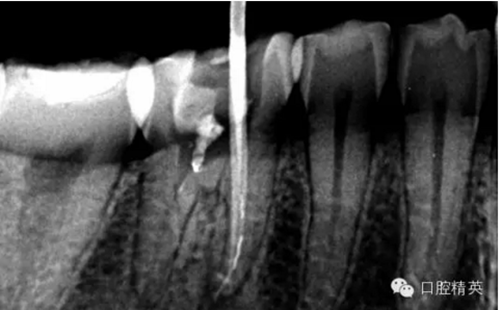

這個(gè)病例是我準(zhǔn)備分根的病例,保留近中根,曾在外院做過干尸長達(dá)數(shù)十年。8號(hào)挫疏通時(shí)近舌根堵,近頰未找到。在這個(gè)病例中首先要知道是為什么根管難以疏通,首先是長時(shí)間的干尸,和患者年紀(jì)較大根管逐漸變窄,根管道路可能會(huì)出現(xiàn)堵塞,在這張病例中我能知道的是稍有不慎就會(huì)形成臺(tái)階,從而導(dǎo)致根管堵塞加重,更加難以疏通。

2.png

近舌8號(hào)k挫疏通,根尖部彎曲,我花費(fèi)時(shí)間2小時(shí)疏通。我個(gè)人覺得根管能否被疏通,第一個(gè)重要因素是時(shí)間,因?yàn)樽鳛檠荔w牙髓的醫(yī)生,首先就是需要的就是耐心。我個(gè)人覺得耐心是非常重要,因?yàn)楹芏喔鼙皇柰〞r(shí),都是我們快要放棄的時(shí)候。所以我每次都會(huì)安慰自己快好了,快好了,就差一點(diǎn)點(diǎn),在堅(jiān)持一會(huì)兒就好了??梢哉f沒有耐心,想做好牙體牙髓,我個(gè)人覺得很難很難。第二個(gè)就是手法,不知道大家啟用挫是什么挫,一般我個(gè)人認(rèn)為,最好從8號(hào)開始疏通,這樣不容易在狹窄的根管內(nèi)形成臺(tái)階(如果有條件的可以從6號(hào)開始)。